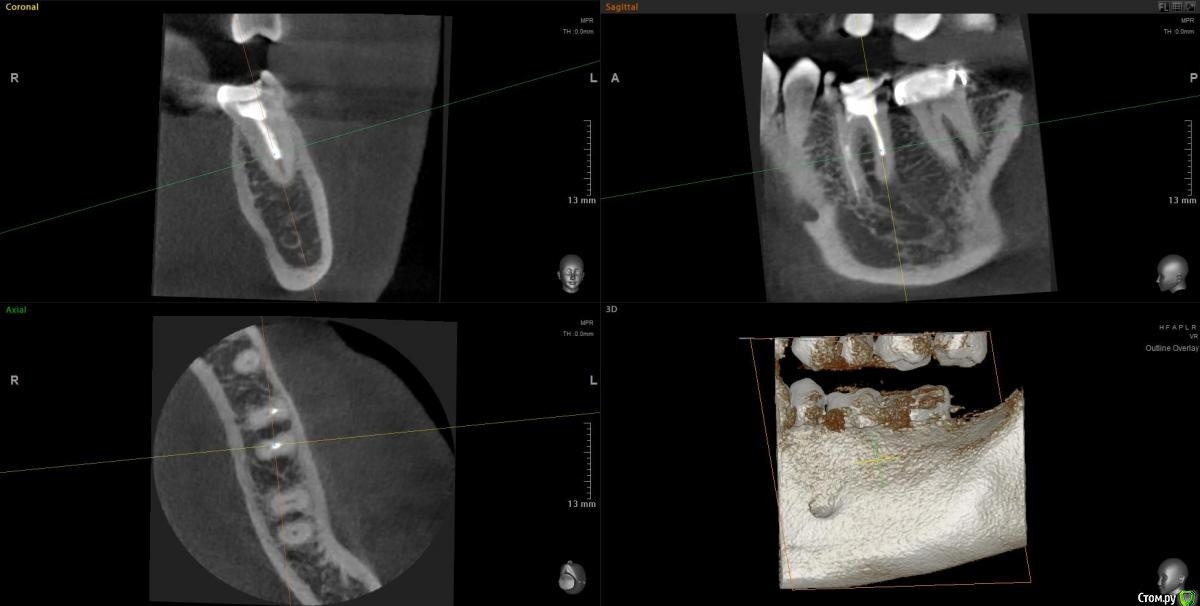

Slava76 Опубликовано 5 декабря, 2020 Поделиться Опубликовано 5 декабря, 2020 Всем доброго дня!Три дня назад с утра появилась боль в нижней челюсти слева. Сначала было не понятно, что болит зуб или мышцы. Но боль шла из под двух крайних коренных зубов. На крайнем зубе коронка, которую установил пару лет назад, зуб живой. У другого зуба пломба, которую установили около 10 лет назад, нервы удалены. Постучал чайной ложкой по этим зубам, боль не усилилась. От холодного, горячего боль так же не усиливается. К вечеру небольшая боль ощущалась только при сжимании зубов. На следующий день с утра все повторилось, с утра болело сильней, к вечеру слабей. Сходил на прием к стоматологу. Сделали снимок, см. вложение. Врач сказал, что у крайнего зуба коронка стоит хорошо, но под коронкой в зубной ткани он видит трещину. Для того, чтобы понять действительно ли она есть и какого размера посоветовал сделать КТ. У зуба под пломбой один канал не долечен, в другом сломали медицинской инструмент. Каких то воспалений он не увидел. Он считает, что боль может вызывать как один, так и другой зуб. Если есть трещина под коронкой, то вылечить зуб нельзя. Только удаление. Если "виноват" зуб под пломбой, то можно перелечить каналы и поставить коронку. В итоге сказал немного подождать, если боль не пройдет, то делать КТ и уже решать. Боль не проходит. Она не сильная, не стреляющая, терпеть ее легко. По ощущениям кажется, что боль идет от зуба под коронкой, но не уверен. Что посоветуете делать дальше? Врач, у которого был, достаточно молод. Хочется услышать еще одно мнение.Заранее благодарю за советы! Ссылка на комментарий

Slava76 Опубликовано 7 декабря, 2020 Автор Поделиться Опубликовано 7 декабря, 2020 (изменено) Сегодня сделал КТ. Выложил здесь https://cloud.mail.ru/public/2ezX/2HwT6HocyНа вечер записался к другому врачу. Послушаю, что он скажет.До обеда при нажатие была небольшая боль. Сейчас практически ее не чувствую. И так уже 4 дня. P.s.1 очень боюсь начать лечить не тот зуб. Коронку очень не хочется трогать. Ей все два года. Делала ее очень хороший врач.P.s.2 может само все пройдет... Изменено 7 декабря, 2020 пользователем Slava76 Ссылка на комментарий

Slava76 Опубликовано 7 декабря, 2020 Автор Поделиться Опубликовано 7 декабря, 2020 Вернулся от врача. Он посмотрел КТ и подтвердил слова DmitrySH. На 90% врач уверен, что проблема из-за не до конца залеченного канала и сломанного инструмента. Сказал, что нужно лечение под микроскопом. У них в поликлинике таких специалистов нет. Завтра начну искать такого врача в Нижнем Ссылка на комментарий

wladdX Опубликовано 7 декабря, 2020 Поделиться Опубликовано 7 декабря, 2020 (изменено) Трещины в зубе 37 не увидел Изменено 7 декабря, 2020 пользователем wladdX Ссылка на комментарий

DmitrySH Опубликовано 5 декабря, 2020 Поделиться Опубликовано 5 декабря, 2020 Под коронкой скорее всего не трещина, а так видно строение зуба. У зуба где сломан инструмент - есть воспаление. Начните с его лечения. Ищите эндодонтиста работающего с микроскопом 1 Ссылка на комментарий